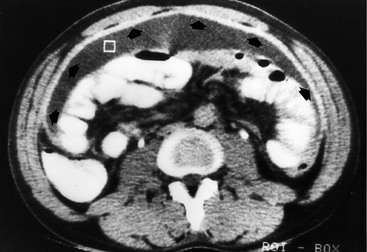

In acute pancreatitis, extravasated pancreatic enzymes may dissect along the mesenteric pathways.1 An extrapancreatic acute fluid collection may spread along the root of transverse mesocolon and, at times, of small-bowel mesentery and extend along the vessels to the vasa recta of the transverse colon and small bowel (Fig. 30-8).5